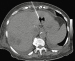

Schima W, Aiginger C Aktuelle Bilder: Gedeckt perforierte Sigmadivertikulitis mit multiplen pylephlebitischen Leberabszessen Journal für Gastroenterologische und Hepatologische Erkrankungen 2015; 13 (2): 18-19 Volltext (PDF) Übersicht

Filmsequenz zu Abbildung 7: Film 3 Kontrastmittelsonographie der Leber im Dualbildmodus (rechts: CEUS; links: normale B-Bild-Sonographie): Die Abszesse zeigen keinen Kontrastmittel- Wash-in oder -Wash-out im Zentrum. |